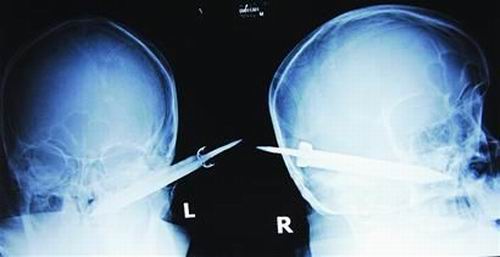

經(jīng)過檢查,醫(yī)生說這把長有10厘米左右的刀,從右耳窩上前方直接刺進(jìn)了鼻腔,離頜內(nèi)大動脈很近,刀卡在了骨頭中,要取出這把刀最怕大出血,萬幸的是這把三棱刀并沒有傷及大腦。

截至昨晚11時(shí)30分,患者頭部刀經(jīng)手術(shù)已取出,生命體征平穩(wěn)。(芮瀟瀟)